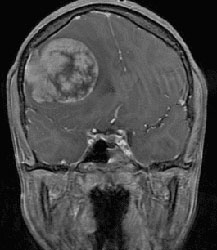

A 12-year-old male presented with a one-month history of nausea and vomiting accompanied by progressive headaches radiating toward the frontal skull and behind the right eye

A brain MRI revealed a 5.7 x 5.5 x 5.0 cm large dural-based extra-axial enhancing mass in the right frontal region of the brain, with a dural tail that was invaginating into the right frontal lobe. As a result, edema and effacement of the right lateral and third ventricles had produced a 10 mm leftward shift—creating significant intracranial pressure.